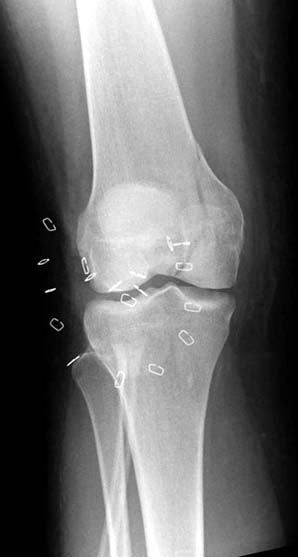

“Перелом наружного мыщелка правого бедра во фрональной плоскости был не замечен”

Диагностическая ошибка происходит, когда игнорируется правила обследования внутрисуставных переломов. Вместо полного обследования, включая КТ, ограничиваются рентгенограммой, и то в одной проекции!

Nork et al, J Orthop Trauma, 87:564, 2005 доложили, что над- и чрезмыщелковые переломы бедра в 38% имеют линию перелома в корональной плоскости!

Спасибо большое за советы! Добавляю некоторые КТ снимки. Перелом коллеги не диагностировали, видимо, расценив костную травму как повреждение задне-латерального комплекса коленного сустава. Отпишусь по результату выполненной операции.